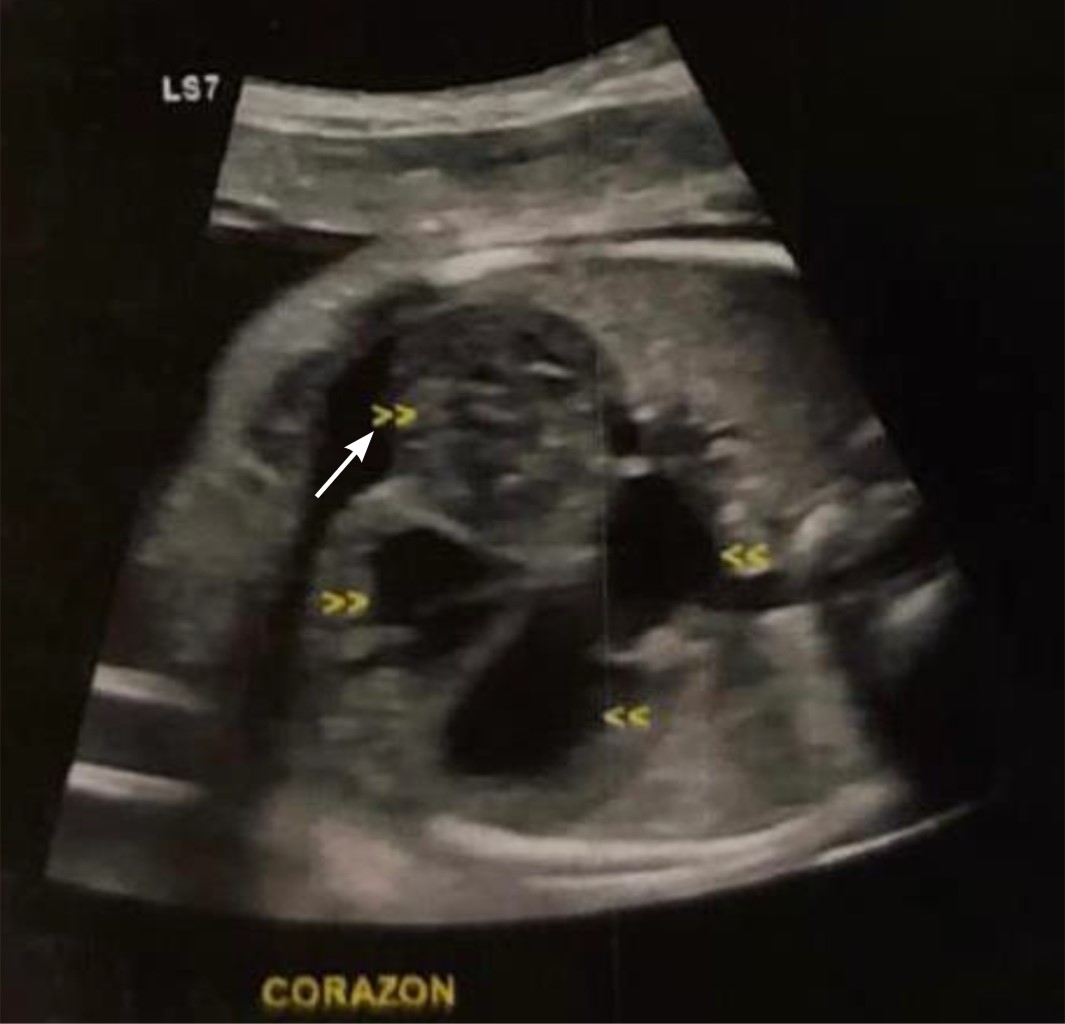

Intracardiac hemangioma in an infant

Introduction: intracardiac tumors in children are rare, but most are benign. In general, these tumors do not cause symptoms, but as they increase in size, they can lead to heart failure. Case presentation: three-month-old male patient who had an intrauterine diagnosis of mediastinal mass. At birth he was asymptomatic. Resection of right atrial tumor was performed. The pathology report indicated that it was an intracardiac hemangioma. The patient has had a favorable evolution. Conclusions: intracardiac tumors are a rare entity in pediatrics, which are generally detected accidentally.

Figure 1